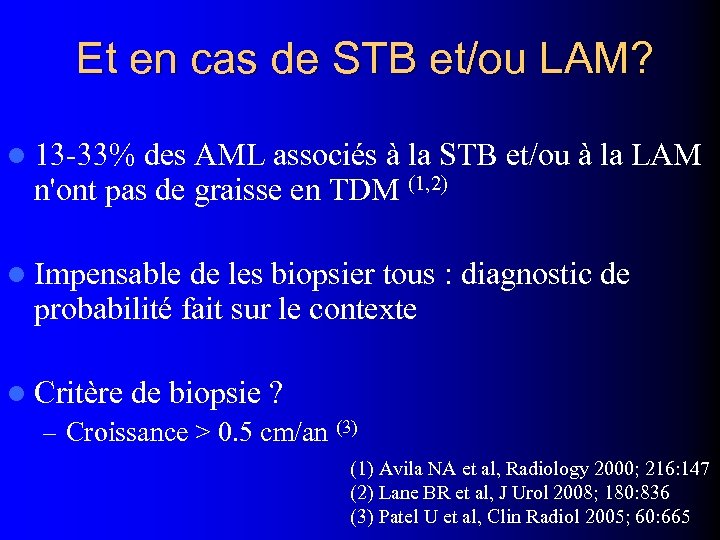

Et en cas de STB et/ou LAM? l 13 -33% des AML associés à la STB et/ou à la LAM n'ont pas de graisse en TDM (1, 2) l Impensable de les biopsier tous : diagnostic de probabilité fait sur le contexte l Critère de biopsie ? – Croissance > 0. 5 cm/an (3) (1) Avila NA et al, Radiology 2000; 216: 147 (2) Lane BR et al, J Urol 2008; 180: 836 (3) Patel U et al, Clin Radiol 2005; 60: 665

Et en cas de STB et/ou LAM? l 13 -33% des AML associés à la STB et/ou à la LAM n'ont pas de graisse en TDM (1, 2) l Impensable de les biopsier tous : diagnostic de probabilité fait sur le contexte l Critère de biopsie ? – Croissance > 0. 5 cm/an (3) (1) Avila NA et al, Radiology 2000; 216: 147 (2) Lane BR et al, J Urol 2008; 180: 836 (3) Patel U et al, Clin Radiol 2005; 60: 665